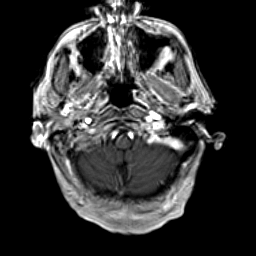

Glioma Overlay -- Slice #2

Click on sagittal image to select slice. Click on thin tickmark to change timepoint, or thick tickmark for overlay.